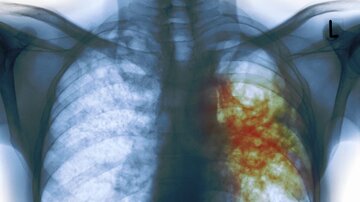

بروز بیماری سل در یک استان

سرپرست دانشگاه علوم پزشکی زابل گفت: طوفانهای گرد و خاک در منطقه سیستان بسیار ویرانکننده است چرا که این پدیده باعث بروز بسیاری از بیماریهای خطرناک مانند سل بین مردم شده است.

وقوع طوفانهای گرد و خاک در منطقه سیستان بسیار ویرانکننده است و خبرنگاران باید به این مسئله به صورت ویژه بپردازند، چرا که این پدیده باعث بروز بسیاری از بیماریهای خطرناک مانند سل بین مردم شده است.